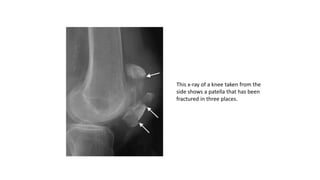

This x-ray of a knee taken from the

side shows a patella that has been

fractured in three places.